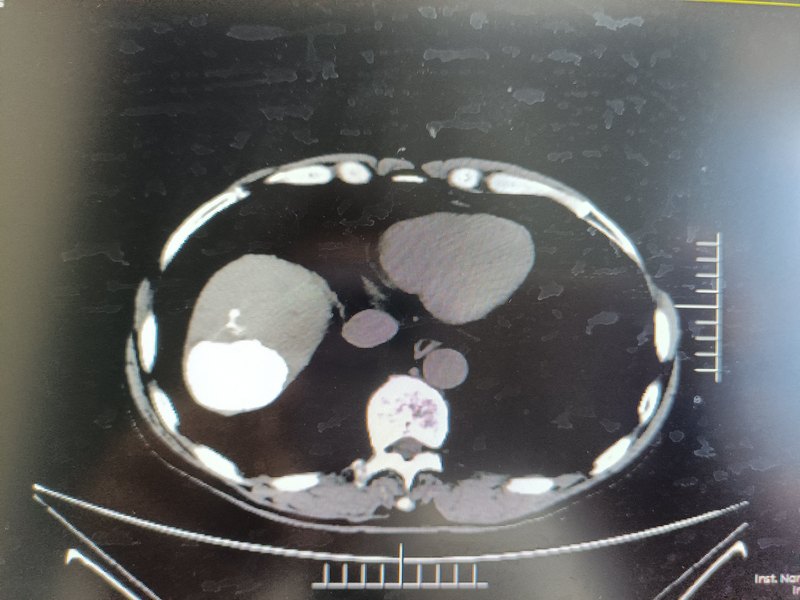

肝癌/肝惡性腫瘤基本是常見惡性腫瘤,是起源于肝細胞的富血供惡性腫瘤,90%血供來自肝動脈。由于起病隱匿,早期沒有癥狀或癥狀不明顯,進展迅速,確診時大多數(shù)患者已經(jīng)達到局部晚期或發(fā)生遠處轉(zhuǎn)移,治療困難,預后很差,如果僅采取支持對癥治療,自然生存時間很短,嚴重地威脅人民群眾的身體健康和生命安全。經(jīng)肝動脈化療栓塞(TACE)是采用的在不開刀暴露病灶的情況下,在股動脈血管、皮膚上作直徑幾毫米的微小通道。在影像設備引導下對病灶局部進行治療的創(chuàng)傷最小的治療方法。治療一方面阻斷腫瘤血供,可以“餓死”腫瘤細胞,同時在腫瘤局部聚集高濃度的化療藥物,可以對腫瘤細胞發(fā)揮最大限度的殺傷作用,被公認為肝癌/肝惡性腫瘤非手術(shù)治療最常用方法。它是非開腹手術(shù)治療肝癌的首選方法,其療效已得到肯定。